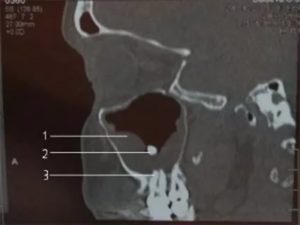

Надежный и информативный диагностический метод. Его эффективность обусловлена внешним видом мицетомы на поздней стадии. В отличие от полипов и раковых клеток, микоз имеет высокую плотность, сравнимую с металлом.

При выведении изображения на томограф, можно заметить объемную шарообразную массу с незначительными структурными изменениями. Плюс метода – полная безопасность для организма, быстрота проведения и возможность использования снимков.

и наиболее информативная методика обнаружения мицетомы — проведение КТ (компьютерная томография). Дело в том, что плотность мицелия аспергилл совпадает с плотностью металла, на получаемых томограммах хорошо виден очаг инфекции. Легко распознать мицелий, который окружён массами, рентгенологическая плотность которых снижена.

Как правило, осмотр не является решающим в диагностике, точное диагностирование проводят лишь при помощи компьютерной томограммы, показывающей грибковое поражение в виде уплотнений.

Рентгенологическая плотность мицетомы сравнима с плотностью металла. На снимке грибное тело отмечается как яркое пятно, которое окружают массы, менее плотные рентгенологически. Реже грибковый шар определяют при помощи МРТ.